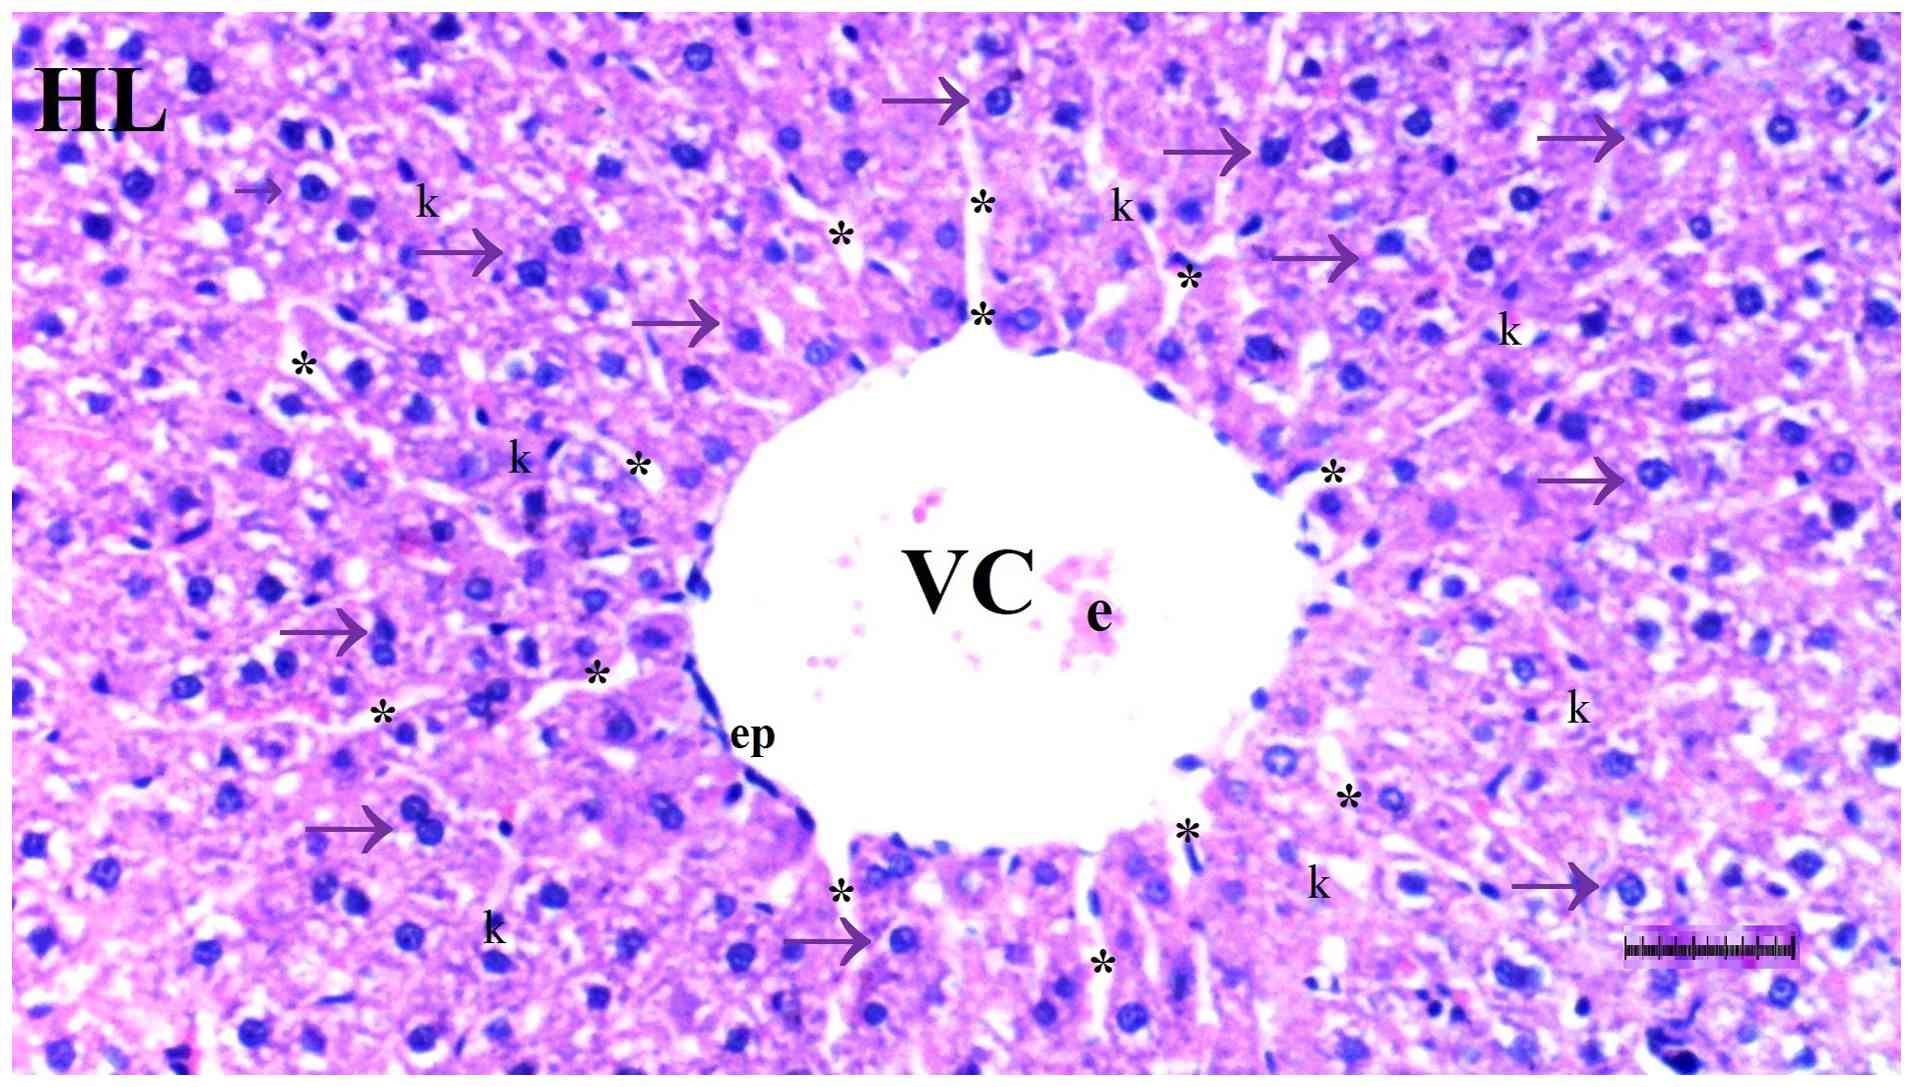

Representative light microscopy of

liver tissue from the group control group. H&E staining.

Magnification, x100. Arrows represent hepatocytes. VC, vena

centralis; HL, hepatic lobule; e, erythrocyte; ep, epithelium; k,

Kupffer cells; *, sinusoids.

Figure 1

Representative light microscopy of liver tissue from the group control group. H&E staining. Magnification, x100. Arrows represent hepatocytes. VC, vena centralis; HL, hepatic lobule; e, erythrocyte; ep, epithelium; k, Kupffer cells; *, sinusoids.

Histopathological examination of liver tissue

Under light microscopy, hepatocyte degeneration differed significantly among groups (P=0.017), being more frequent in the DM/SEP group compared with the S and D groups (P=0.001 and P=0.013, respectively). However, it was significantly reduced in the FUL/C-60 group compared with that in the DM/SEP group (P=0.042) (Table I; Fig. 1, Fig. 2, Fig. 3 and Fig. 4).

Sinusoidal dilatation also differed significantly among groups (P=0.022), being more prominent in the DM/SEP group compared with the S group (P=0.002) and significantly lower in the FUL/C-60 group compared with the DM/SEP group (P=0.013) (Table I; Fig. 1, Fig. 2, Fig. 3 and Fig. 4).

The presence of pyknotic cells differed significantly among groups (P=0.044). Pyknotic cells were more commonly observed in the DM/SEP group compared with the S and D groups (P=0.003 and P=0.037, respectively), whereas pyknotic cells were significantly fewer in the FUL/C-60 group compared with the DM/SEP group (P=0.037) (Table I; Fig. 1, Fig. 2, Fig. 3 and Fig. 4).

The number of cells undergoing necrosis differed significantly among groups (P<0.001). More necrotic cells were observed in the DM/SEP group compared with the S and D groups (P<0.001 and P=0.004, respectively). Furthermore, the number of necrotic cells was higher in the FUL/C-60 group compared with the S group (P=0.012), but significantly lower in the FUL/C-60 group compared with the DM/SEP group (P=0.040) (Table I; Fig. 1, Fig. 2, Fig. 3 and Fig. 4).

Mononuclear (MN) cell infiltration in the parenchyma was significantly different among groups (P=0.035). MN cell infiltration was more pronounced in the DM/SEP and FUL/C-60 groups compared with the S group (P=0.004 and P=0.040, respectively) (Table I; Fig. 1, Fig. 2, Fig. 3 and Fig. 4).